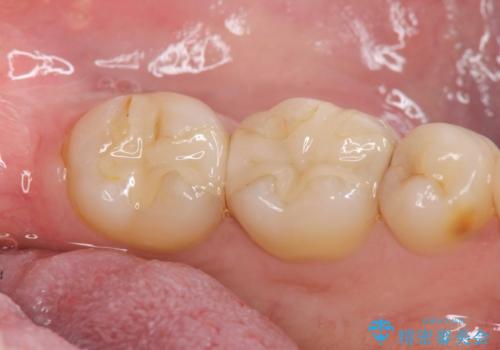

- 12万円 ゴールドインレー×2費用は治療当時の料金となります

ゴールドインレーについて

ゴールドは見た目に難がありますが、歯を削る量がセラミックに比べて少ない・複雑な形にも追従しやすい・壊れにくいなどの利点があります。

PGA(ゴールド)クラウン、インレーの注意事項(リスク・副作用など)

- インレーおよびクラウンは脱離するリスクがあります

- 形成量はセラミックより少ないですが、歯の形成、修復後に歯に症状が出ることがあります